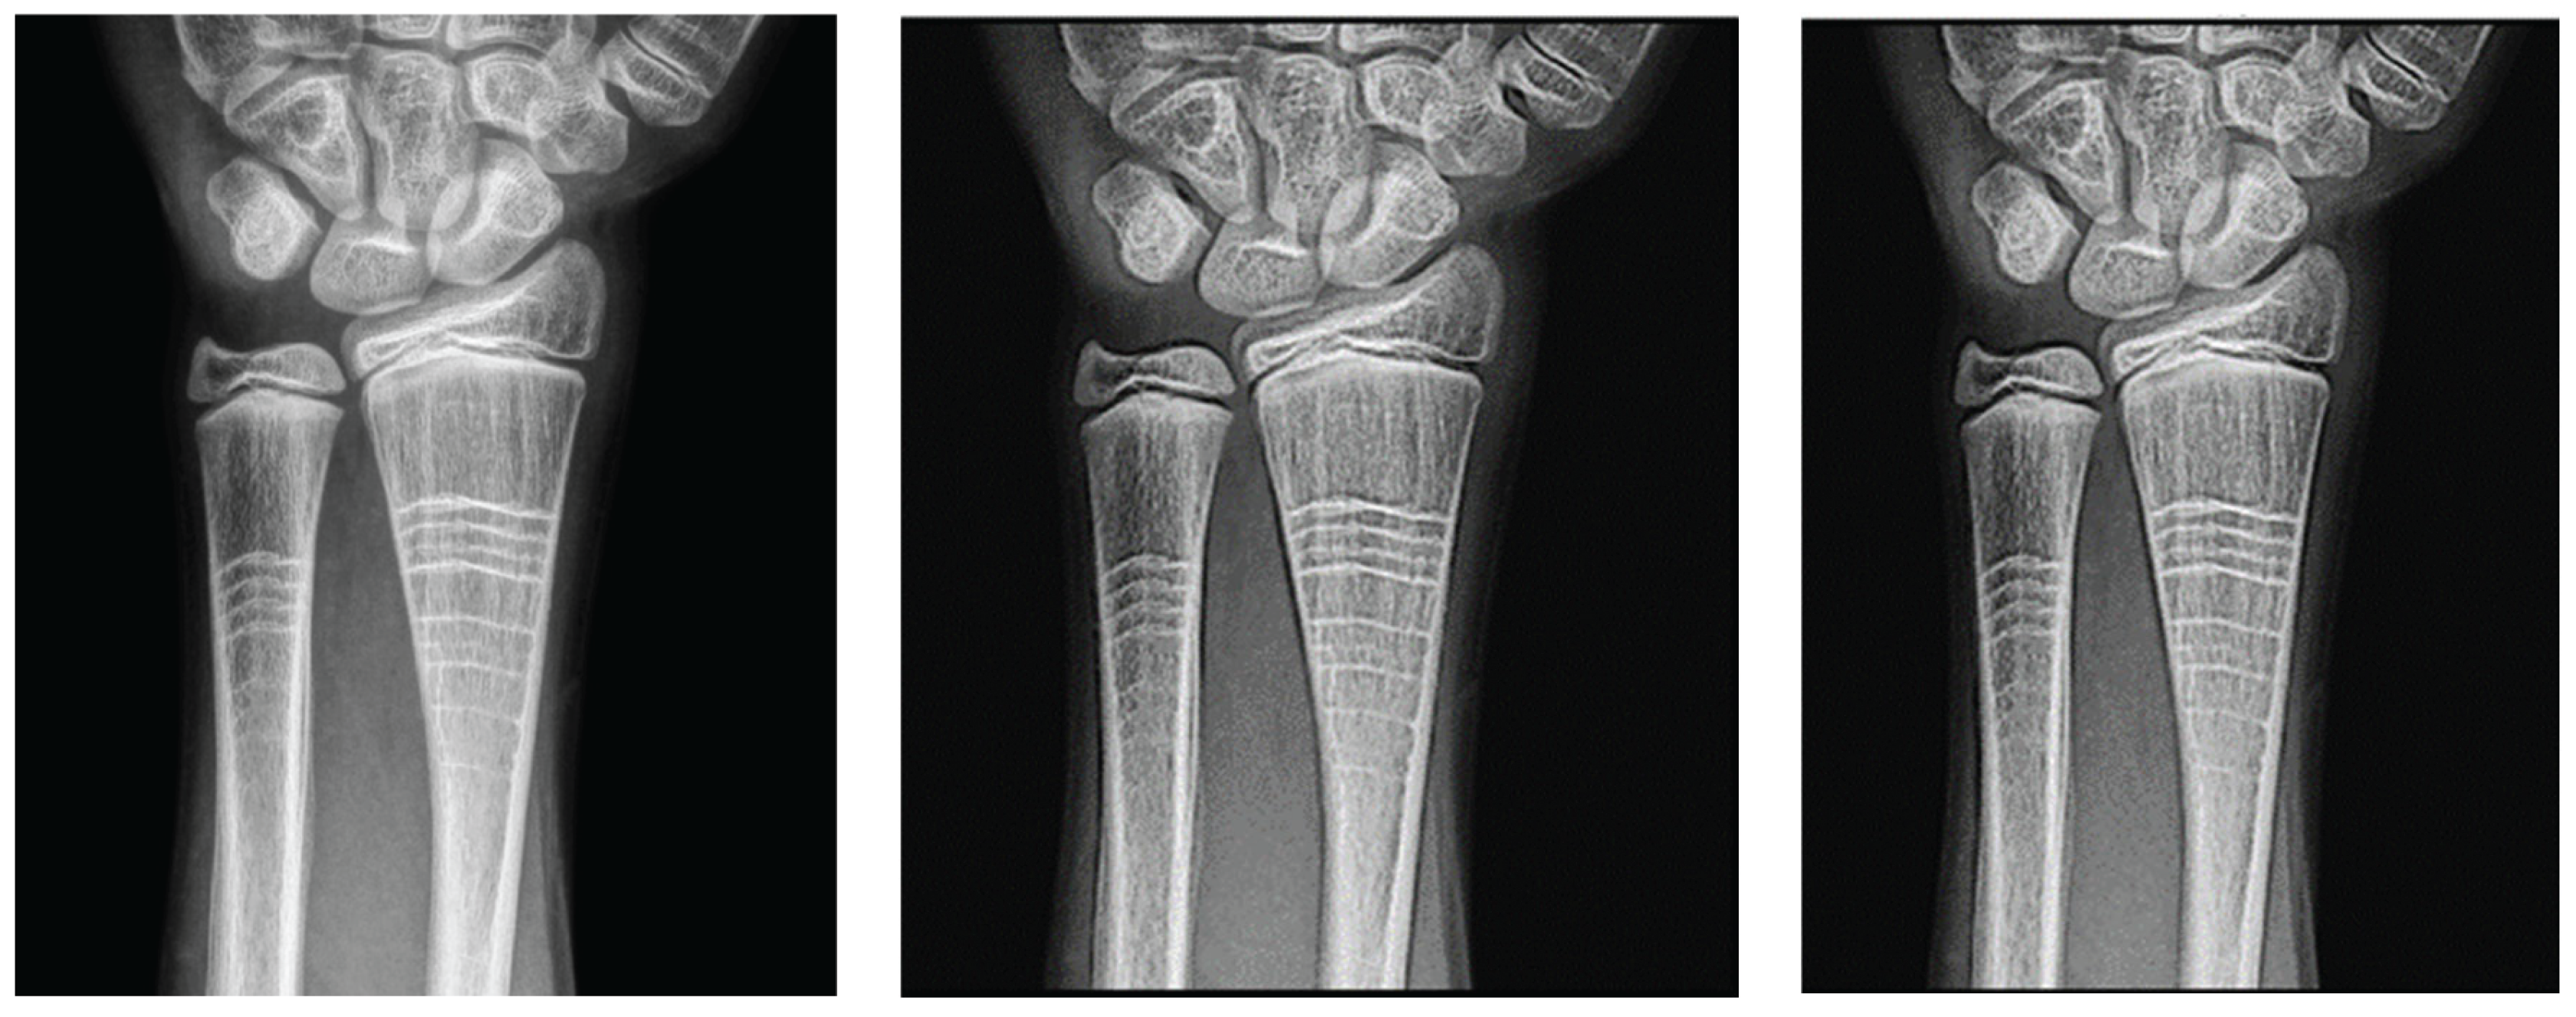

Wrist radiographic images processed with values close to d = 1.4 (Figure 7) show greater sharpness and detail, as in the case of the knee. The contrast improves steadily up to d = 1.4, as shown in Table 3. Entropy increases slightly, maintaining noise levels. The maximum contrast value is 3.76 at d = 4.4, which is a 38% improvement. Visual inspection confirms that the filter works in small, highly detailed regions.

In wrist images, the contrasts were ascending and crossed earlier than in other cases (Figure 8). Entropy also presented an ascent (Figure 9).

Table 3 shows the contrast and entropy values for different d values in the wrist image. As with the knee image, both filters achieve an increase in contrast, with a crossing of the curves earlier than in other cases. Entropy also presents an ascent but maintains reasonable values.

The reported improvements of 45% for knee images and 38% for wrist images are consistent with the contrast metric gains in Table 1 and Table 3, respectively. The optimal d values and maximum contrast gains relative to the input images are reported in these percentages.

The results obtained demonstrate the effectiveness of the proposed algorithm in improving contrast and sharpness in radiographs, especially in images of the knee (Figure 1) and wrist (Figure 7). Figures 2, 5, and 8 show the contrast behaviour, and Figures 3, 6, and 9 show the entropy as a function of the parameter d for each image type. This implies that the filter reduces the reported scattering effects and tissue heterogeneity. In knee images, where higher energies are used (50 keV or more), Compton and photoelectric effects predominate. In these cases, the proposed filters successfully modelled image degradation due to radiation scatter, which was reflected in a significant improvement in contrast and sharpness.

Figure 7. Original image (a) obtained from the wrist for d=1.4, with filter 1 (b) and filter 2 (c).